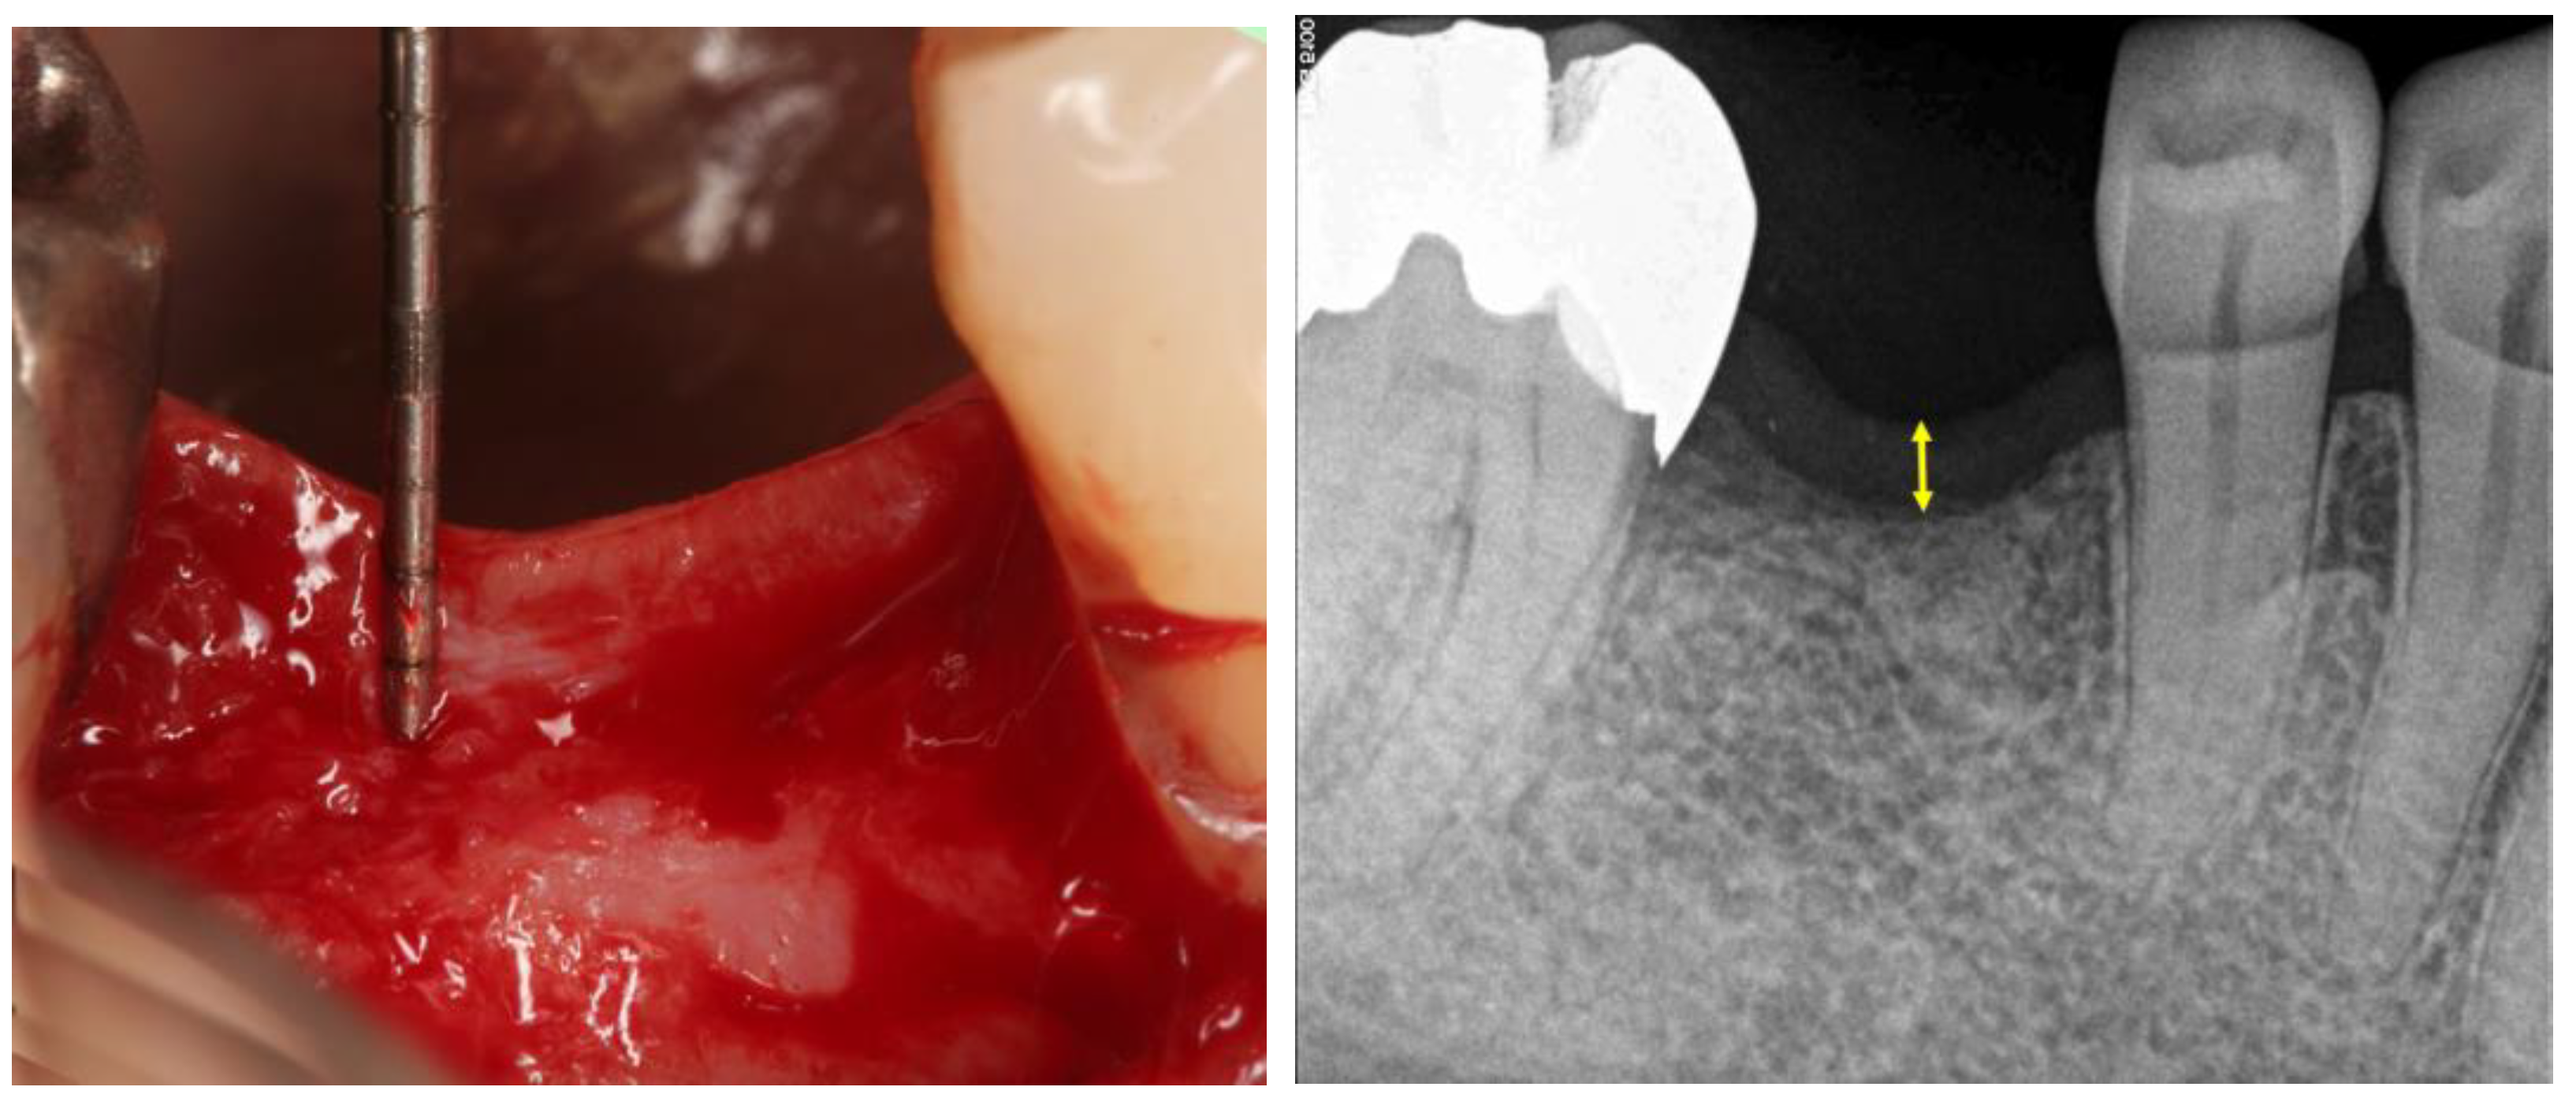

The comparative data measured between mesial and distal marginal bone loss with the observed variables. Overall mean of mesial and distal MBL were 1.11 ± 1.16 mm and 1.11 ± 1.15 mm, respectively, resulted in non-statistically significant differences (p > 0.05). The comparison of the bone loss between the patient’s sex showed non-statistically significant differences (p > 0.05), where the woman patient’s show an MBL mean value of 1.1 ± 1.25 mm and the man patient´s 1.0 ± 0.93 mm. The images of the Figure 6 show a sequence of measurements of the MBL.

Figure 6.

Radiograph sequence used to evaluate and measure the bone level. The measurements were performed from the implant platform to the crestal bone (red arrows = m-MBL and green arrows = d-MBL).